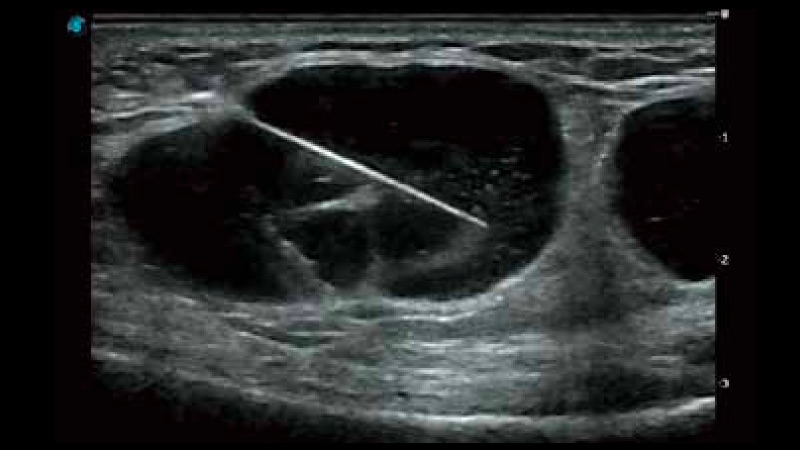

穿刺增强

穿刺增强通过超声波光束控制和偏转,增强了针头在组织中的显像效果。从而保证在穿刺过程中最大限度减少对周围组织的伤害,降低穿刺风险,提高穿刺成功率。